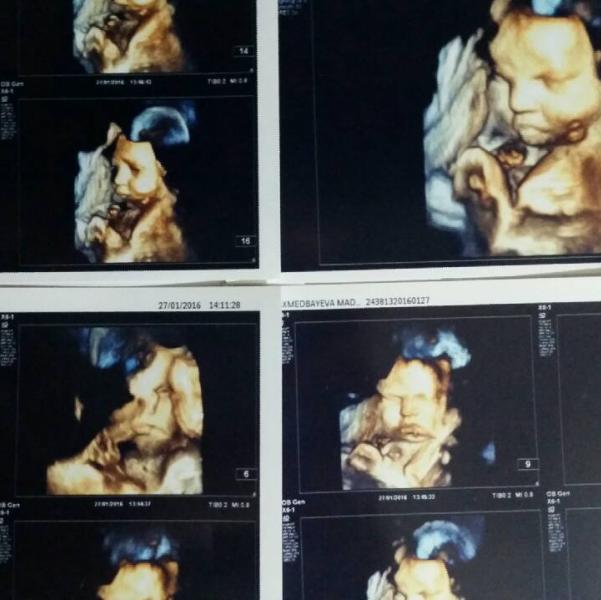

Всем доброго времени суток) В первую очередь с вами поделюсь девочки!!) Пошла я все таки в Федорович на доплер 3d. Ой ну это суппер! Всем рекомендую только туда! Фотки даже качественнее чем того которого сюда с инета ставила. Я такая счастливая!)) получилось даже лучше чем ожидала! Расположение Р тоже идеальна (как У сказала) и личико открывал и язык показывал и брови морщил и ручкой "помахал".....я в экстазе....... ну все классно было..... Я сегодня в эмоциях усну 😊 ______Кстати____тем кто ждёт что бы Р подрос и потом на снимки....оказывается наоборот слишком поздно (как я) не советуют. Оказывается чем больше тем сложнее момент ловить и на фотках получится не все тело а вот как у меня.....только лицо и плечи ели как.... Сказали самый лучший срок для снимков 25-30 нед

@farisha_05 Ой не знаю 😊 Я не очень в таких снимках разберуаюсь....) В тех которых мне дали с края написано 4D получается что эти не 3 а 4d да?